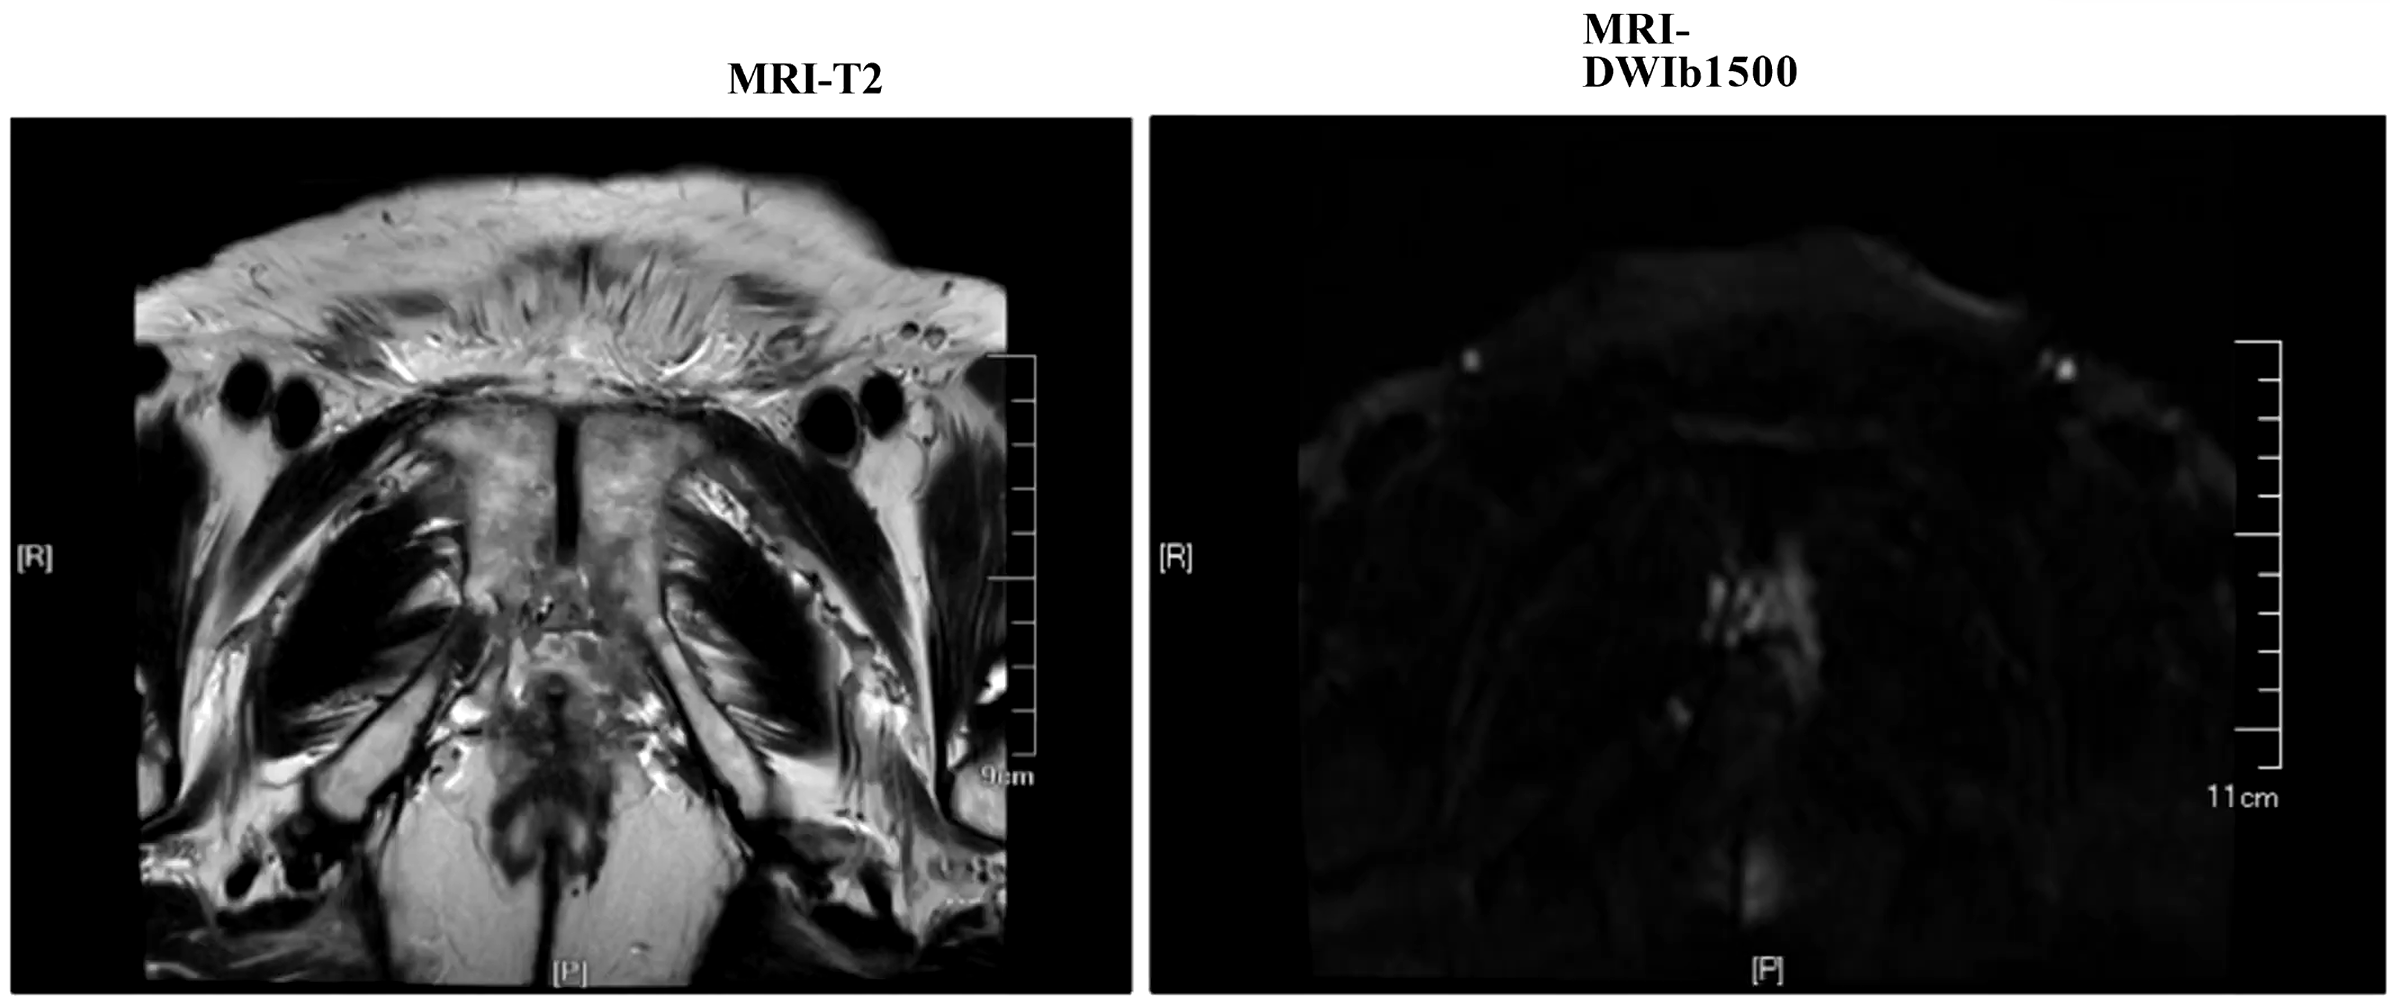

• MRI:新辅助治疗后体积明显缩小,精囊信号不均,膀胱后壁分界不清;未见精囊膀胱侵犯,未见淋巴结转移

• PSA:0.26ng/ml

图片2.png